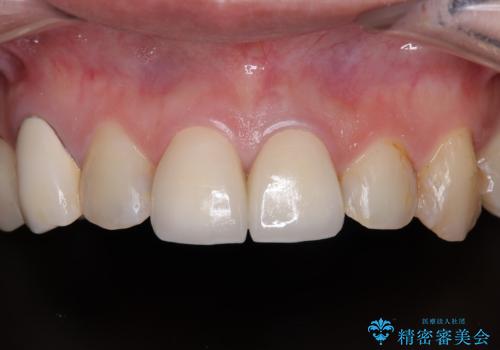

神経が露出しないよう慎重に行った結果、神経を保存することができました。処置後に多少の痛みが生じましたが、その後は良好な状態が続いています。

色、形ともに、自然な仕上がりとなり、患者様には大変満足していただきました。